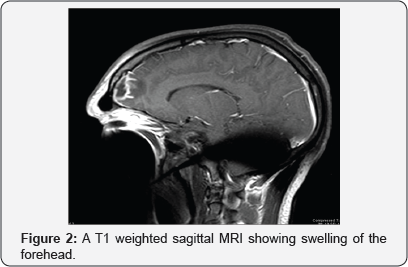

Imaging studies were conducted and showed what appeared to be an epidural collection in the frontal area, right frontal sinusitis, and ethmoid sinusitis with preseptal cellulitis and extension into epidural space in the frontal region. MRI showed paranasal sinus opacification with intracranial extension, extraaxial empyema formation, dural and leptomeningeal enhancement with some focal meningitis. These findings were consistent with Pott's puffy tumor, a rare syndrome associated with frontal sinusitis (Figure 1-3).